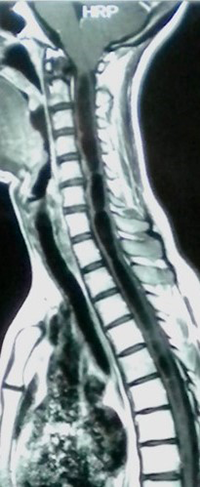

La siringomielia (SM) es una dilatación quística de la médula espinal de forma, tamaño y extensión variables, secundaria a una obstrucción en la circulación normal del líquido cefalorraquídeo (LCR), localizada en la fosa posterior (Chiari, quistes aracnoideos, etc.) o en el canal espinal (aracnoiditis, espondilosis, etc.) 1 (Figura 1).

Figura 1:

RM sagital ponderada en T1 que muestra una siringomielia cervicodorsal causada por una malformación de Chiari tipo 1.